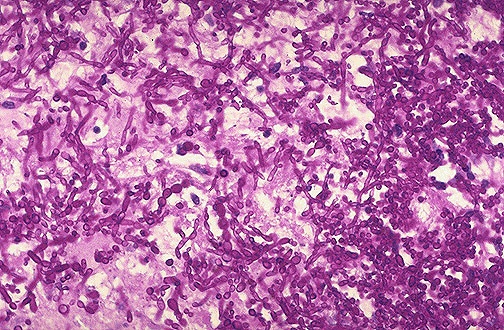

Candida albicans is seen here as an invasive process in the esophagus with PAS staining.